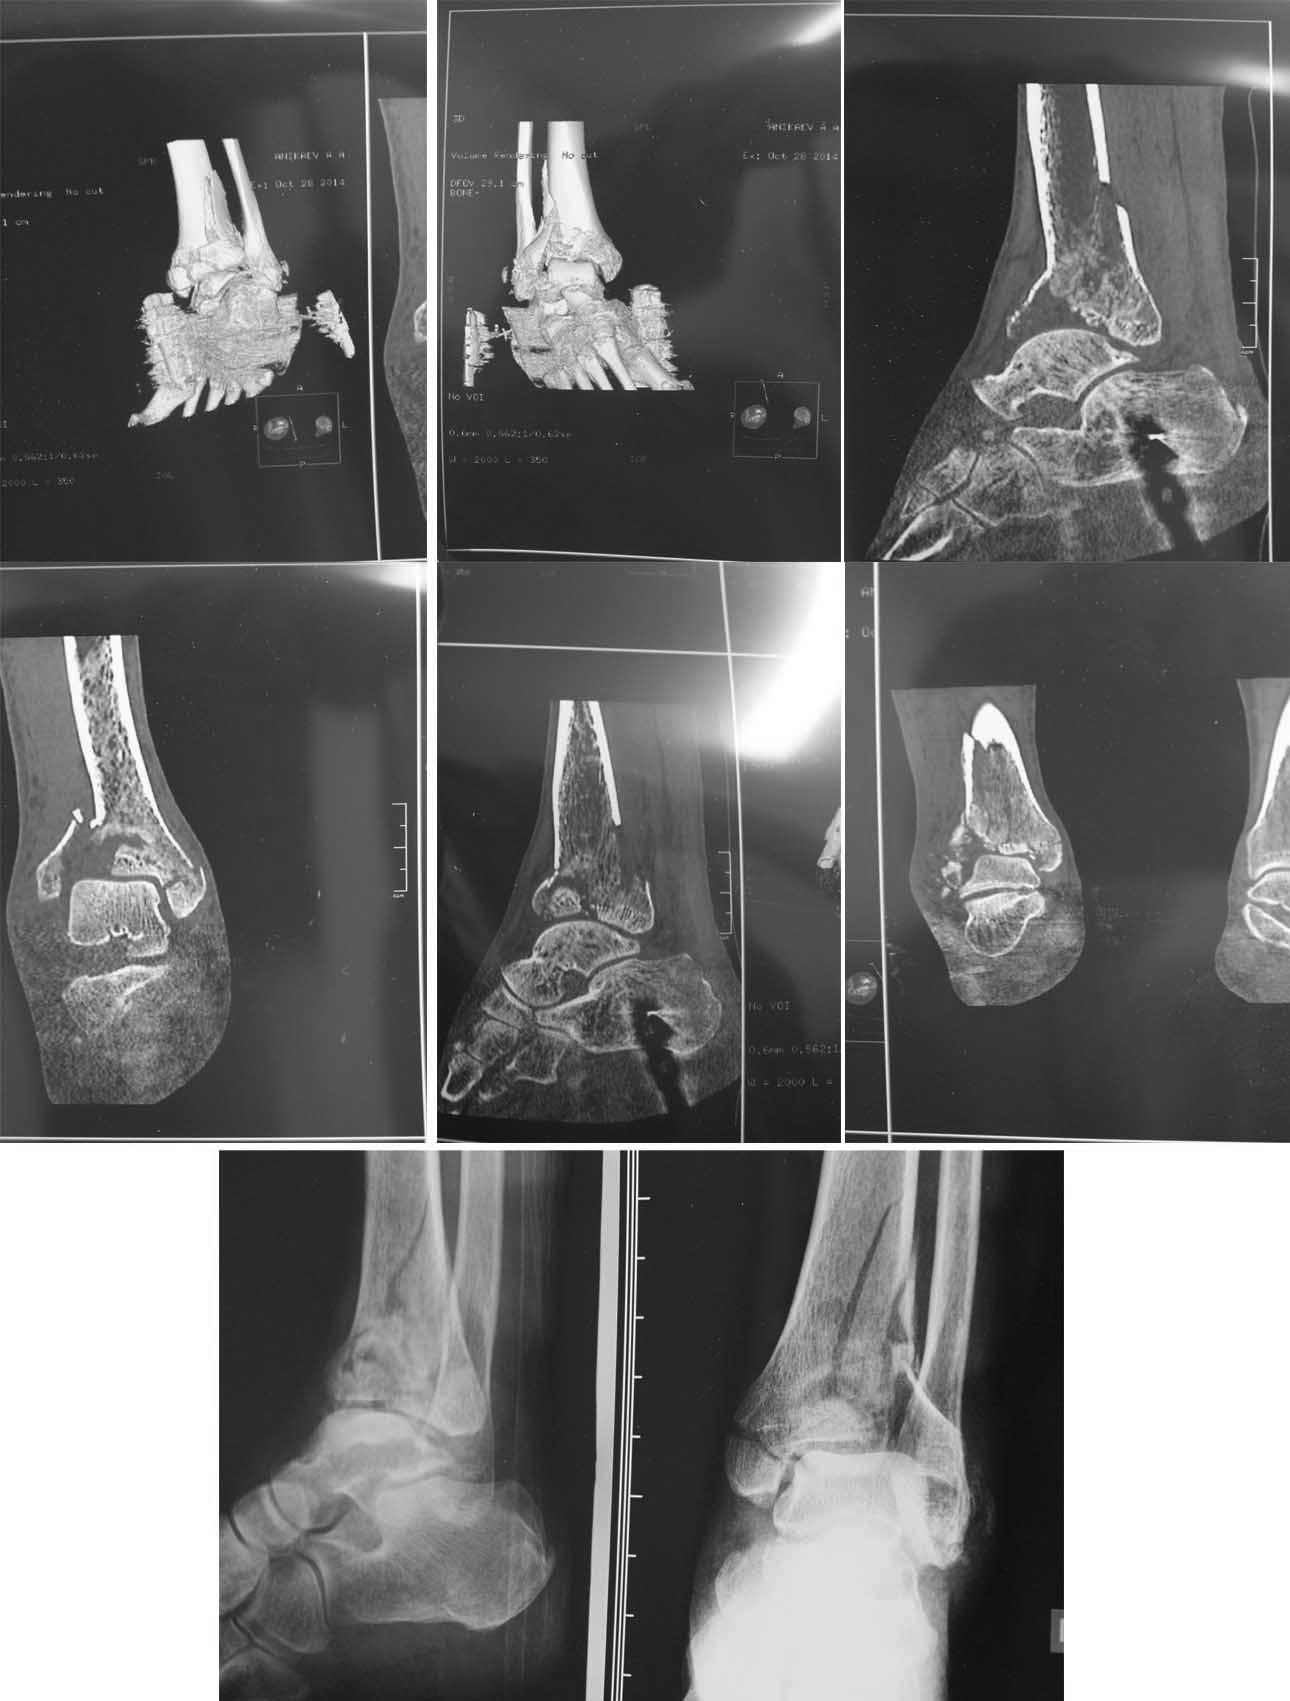

Добрый день, уважаемые коллеги! Мужчина 52 лет, упал с высоты

трёх-четырёх метров 23.10.14. Закрытый перелом пилона.

Малоберцовая кость целая (на всём протяжении сделали Rg).При поступлении

наложено скелетное вытяжение. Отёк, фликтены. Перевод скелетного

вытяжения на дистрактор (спица в пяточной кости, спица в бугристости

большеберцовой кости, полукольца, телескопические штанги). На данный

момент: отёк купируется, фликтены заживают. Мужчина без вредных

привычек, работает электриком-монтажником.

Наш план: -передний, или передне-латеральный доступ (для пластины типа

pilon, Рыбинск, или антеро-латеральной пластины). Или передне-

медиальный (пластина типа "лист клевера").

- Отвести отломки переднего края, ревизия суставной поверхности.

-Костная пластика аутокостью.

-Установка латерального фрагмента, который держится связкой синдесмоза с

малоберцовой костью на своё место.

-репозиция отломков переднего края.

Провизорная фиксация спицами.-установка пластины. Медиальный комплекс

фиксировать спицами или винтами при передней установке пластины.

Смущает большой дефект по латеральной суставной поверхности

большеберцовой кости.

Какова наиболее оптимальная тактика лечения на ваш взгляд? Каким

доступом лучше воспользоваться? Кукую металлоконструкцию выбрать?Заранее

благодарен!